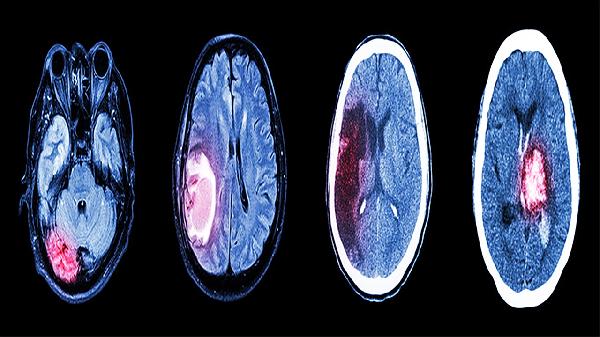

闭合性颅脑损伤后遗症主要有头痛头晕、认知功能障碍、情绪障碍、运动功能障碍、癫痫发作等。闭合性颅脑损伤是指头部受到外力作用,但颅骨保持完整,脑组织受到损伤的一种情况。